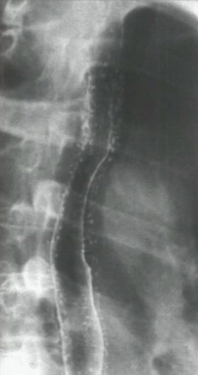

What could cause this?

Pseudodiverticulosis. This is a result of chronic inflammation or irritation of the submucosal glands that causes tiny outpouchings.